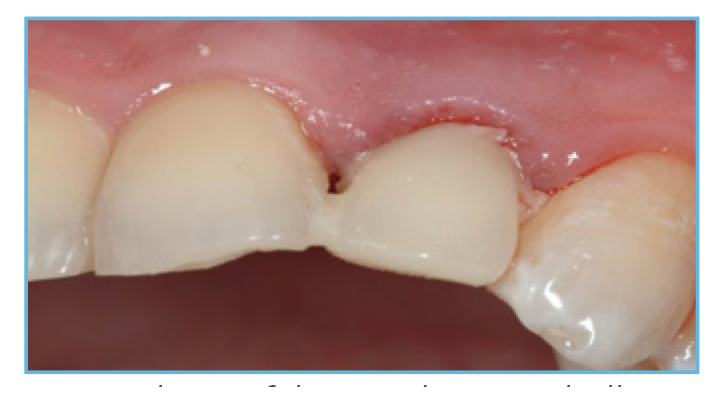

Fig. 4. The prefabricated crown shell was luted to the PreFormance Post.

Fig. 5. The provisional restoration was fabricated, occlusal and interproximal contacts were checked, adjusted accordingly, and delivered to the patient.